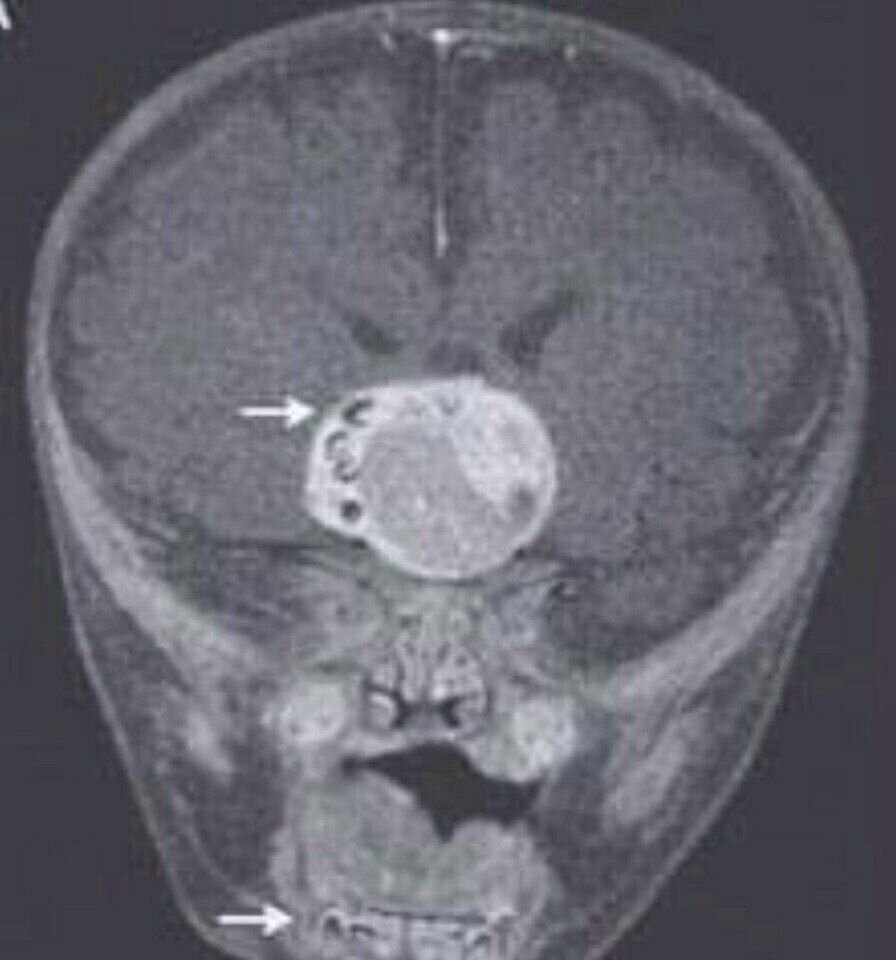

4-месячного ребёнка прооперировали по поводу опухоли головного мозга. При анализе выяснилось, что содержимое опухоли - зубы. Тератома - доброкачественная опухоль, представляет собой ткань или даже орган, нетипичныйдля локализации опухоли: в тератоме могут присутствовать волосы, мышечная ткань, костная ткань, реже более сложные органы — зачатки глаз, туловища, конечностей.

4-месячного ребёнка прооперировали по поводу опухоли головного мозга. При анализе выяснилось, что содержимое опухоли - зубы.

Тератома - доброкачественная опухоль, представляет собой ткань или даже орган, нетипичныйдля локализации опухоли: в тератоме могут присутствовать волосы, мышечная ткань, костная ткань, реже более сложные органы — зачатки глаз, туловища, конечностей.